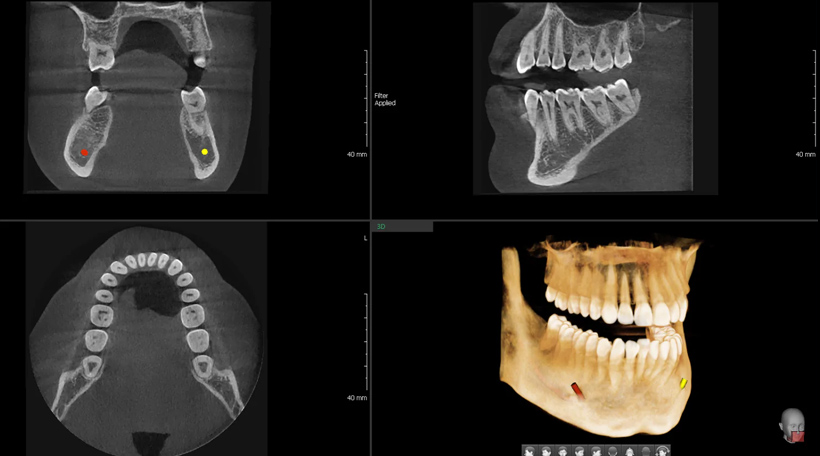

TOMOGRAFIA COMPUTERIZATĂ CBCT – CT 3D

Tomografia computerizată CBCT – FOV 8X8 CM

Tomografia computerizată dentară se recomandă în cazul unor tratamente endodontice (de scoatere a nervului), implanturi dentare şi manopere de chirurgie buco-maxilo-faciale. Pe acest computer tomograf medicul poate face măsurători foarte precise la nivelul osului, (poate măsura lungimea, lăţimea, înălţimea şi densitatea osoasă), poate vedea existenţa tumorilor, fracturilor, traiectul nervilor etc.